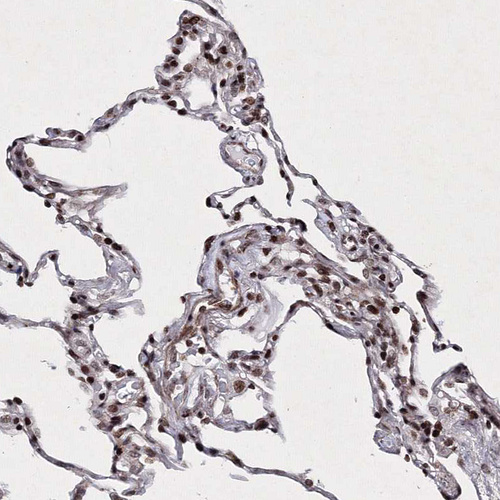

Immunohistochemical staining of human cerebral cortex shows strong nuclear positivity in neurons.